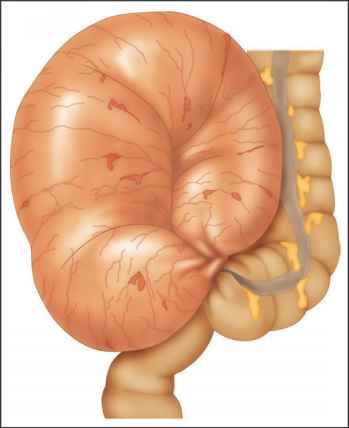

The young girl had been treated for bloating and constipation problems since birth. A post-mortem examination showed Keziah had sigmoid colon volvulus, a rare stomach condition that causes the colon to twist.

Dr. Andreas Marnerides, the pediatric pathologist who carried out her post-mortem exam, said: “When it twists enough the blood supply is cut off and this can kill the colon and be fatal.”

Coroner Veronica Hamilton-Deely said that even an X-ray may not have revealed the condition. She said the girl’s cause of death was a damaged colon due to twisting.